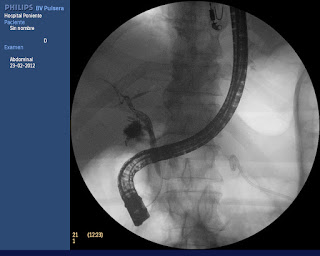

Paciente varón de 53 años, sin antecedentes de interés, intervenido por vía laparoscópica de una colecistitis aguda litíasica en otro centro. Fue dado de alta a las 72 horas con buena evolución. A los 4 días del alta hospitalaria acude a urgencias de nuestro hospital por fiebre, dolor abdominal de moderada intensidad, progresivo, localizado en hemiabdomen superior (especialmente en HD) junto a distensión abdominal, nauseas, vómitos y subictericia. En la exploración física no había signos de irritación peritoneal, pero si dolor a la palpación y distensión abdominal. Analíticamente destacaba únicamente una BRT de 3.7 mgr/dl, a expensas de la fracción directa. La ecografía realizada mostraba una colección catalogada como biloma, a nivel subhepático (gastrohepático), colocándose un drenaje pigtail con la obtención de abundante material bilioso. Debido al mantenimiento de un débito biliar importante por dicho drenaje (> 500 cc cada 24 horas), se decide realizar una CPRE con papilotomía y colocación de una prótesis biliar. En dicha intervención, se canula la vía biliar con técnica de precorte de aguja (NK-EST) previa colocación de una prótesis pancreática de 5 c/5 Fr, se confirma la fuga de contraste en el muñón cístico para finalmente colocar una prótesis biliar de 8.5 Fr y 10 cm de longitud que consigue sellar la fuga. A las 48 horas el débito por el drenaje percutáneo desaparece y el control ecográfico muestra una importante redución de la colección descrita.